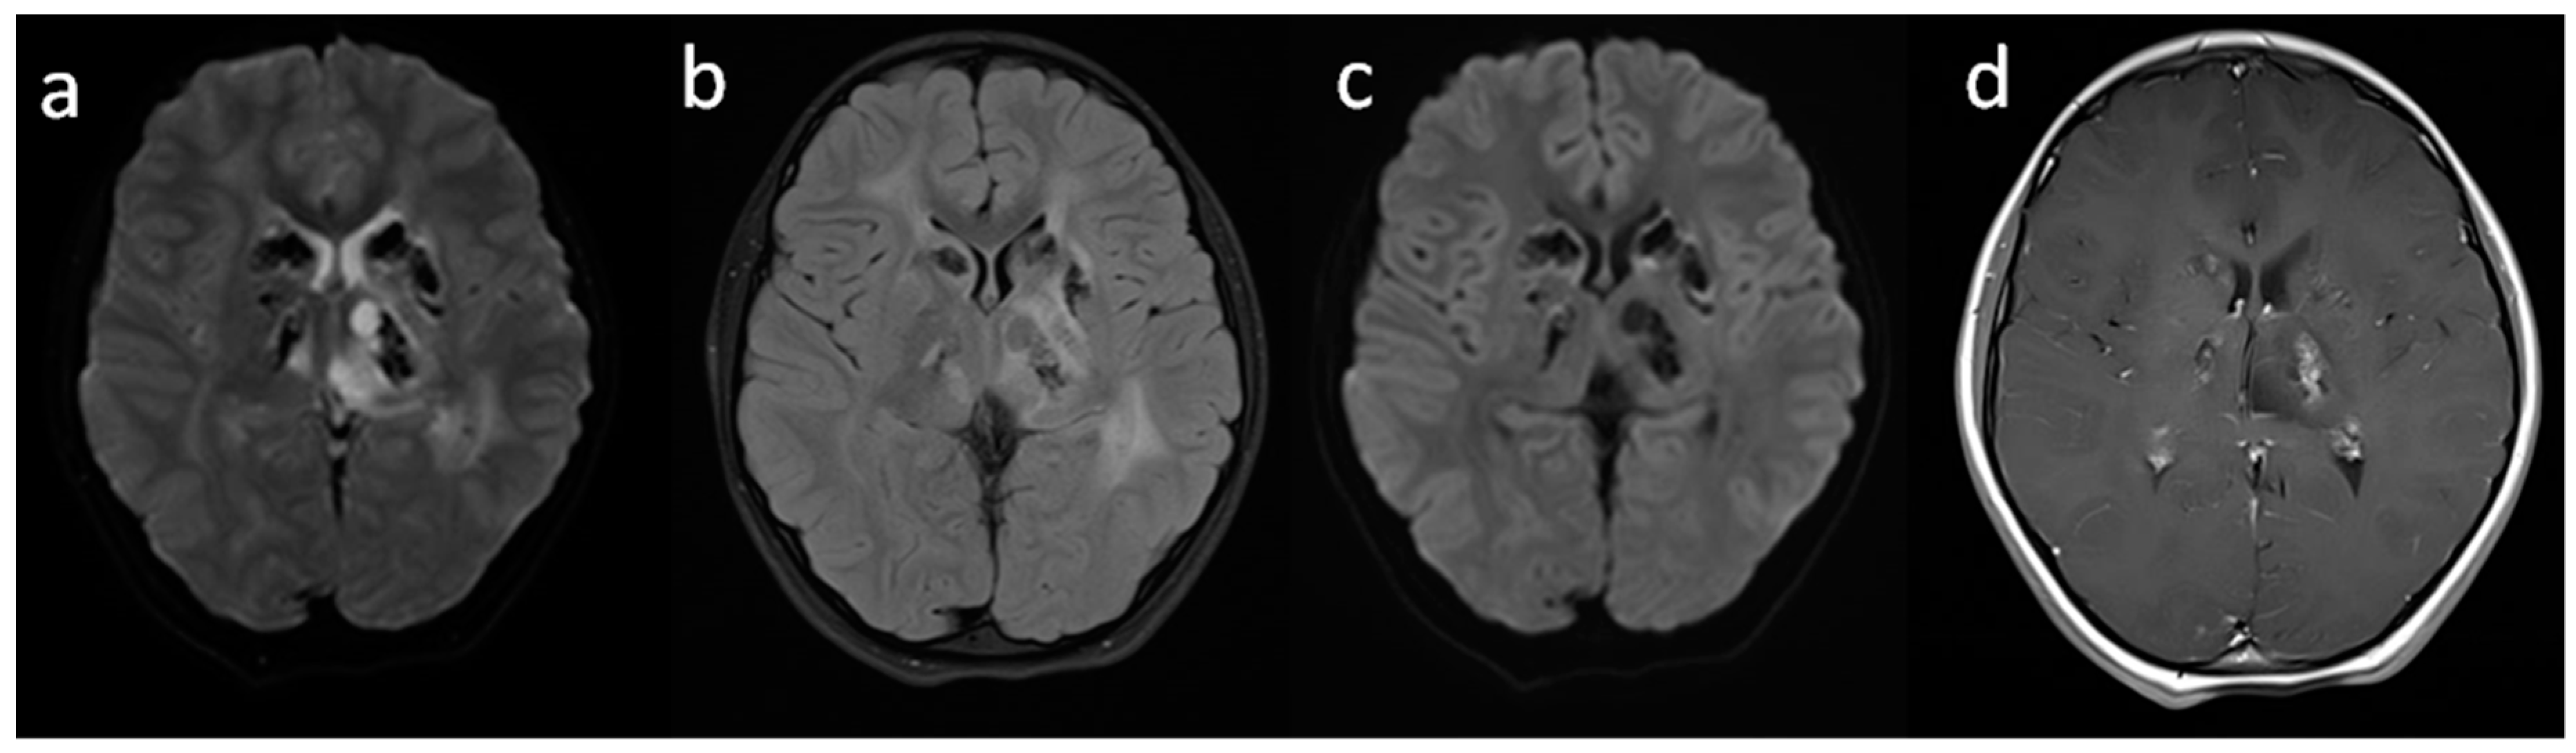

2. Case Report